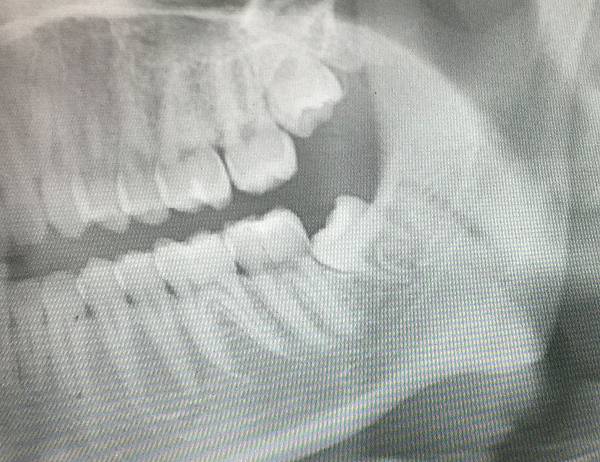

手術前確認X光片預先了解牙齒的位置與角度

全口片可以預先知道牙根型態相關神經位置